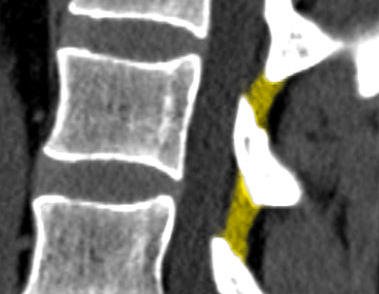

Normalne więzadła żółte w tomografii komputerowej

Przerost więzadeł żółtych to jedna z form zwyrodnienia kręgosłupa. Wraz z wiekiem struktury te tracą sprężystość i zwiększając swoją grubość, zabierając tym tym samym więcej miejsca w kanale kręgowym, a ściślej w jego zachyłku bocznym. Kiedy tego miejsca jest ciągle wystarczająco dużo, pogrubienie nie powoduje objawów.

Jednak u niektórych osób kanał kręgowy jest wąski. Może to być wrodzone, albo spowodowane przez zwyrodnienie kręgosłupa, szczególnie przez przerost stawów miedzywyrostkowych, osteofity oraz dyskopatię. Łącznie te zmiany mogą powodować ucisk na worek oponowy, korzenie nerwowe lub rdzeń kręgowy. Najczęściej przerost występuje w odcinku lędźwiowym na poziomach L4L5 i L5S1.

Pogrubiałe więzadła żółte w kręgosłupie ze zwężeniem kanału kręgowego